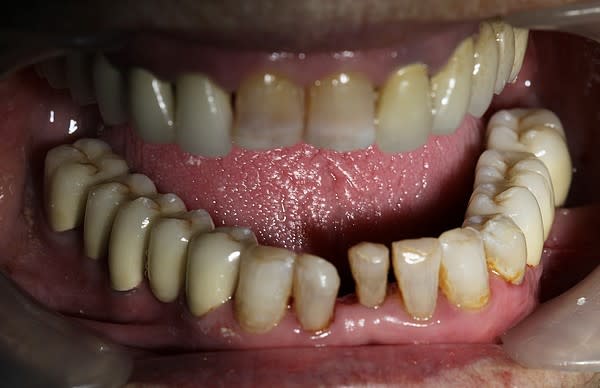

Cette même patiente, pimpante pour ses 90 ans et pleine de gaieté, viens me voir pour son nouvel appareil du bas qu'elle ne supporte pas. Avec surprise, je découvre dessous des chicots abandonnés par son ancien dentiste avec des inflammations gingivales. Radios prises, je lui propose de tenter de les récupérer pour lui réaliser des bridges en remplacement de son appareil, à l'inverse de ce qui se fait habituellement.

La racine résiduelle de la 37 était logée au fond d'un entonnoir gingival au ras de l'os et la 46 était trop délabrée pour la conserver entière. Après quelques séances de gingivoplasties et de tailles, le pari était gagné et les bridges ont pu être scellés, la patiente était radieuse!